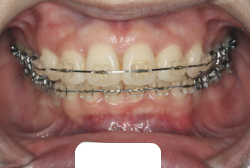

歯科矯正用アンカースクリューを用いた症例(骨格性反対咬合 非抜歯治療)

「ものがうまく噛めない」という主訴で来院したケースです。診断の結果、「骨格性反対咬合に伴う咬合不良+軽度叢生」と判明しました。原因としては特に下顎の左側が過成長したため、骨格性反対咬合になり、特に左側での噛み合わせが非常に悪くなっていると診断しました。初診時の写真を見ると、上下の正中線の大きなズレ、左側の噛み合わせの不良がはっきり分かります(黄色の矢印と緑の矢印は一致しているのが正しい状態です)。

そもそも、このような状態となっているのは骨の大きさに問題があるため生じていますので、場合によっては、「外科矯正」によって下顎の骨を外科的に縮めることで修正します。患者様が外科矯正をご希望されない場合は、従来ですと上下左右の小臼歯抜歯を行い矯正するのが普通です。

今回の患者様の場合は、「外科」も「小臼歯抜歯」も拒否されましたので、歯科矯正用アンカースクリュー(以下 アンカースクリュー)を用いて、下顎の歯列全体を後方に下げるという方法を取りました。

治療中の写真で、アンカースクリューより歯を後ろへ牽引しているのがお分かりいただけるかと思います。牽引を1年ほど続け、途中補助的に上下にゴムをかける(これを顎間ゴムと言います)手法なども追加し、全体で21ヶ月で治療を終えることが出来ました。

結局歯の本数を減らすことなく、すべてご自分の歯を残して、正しい配列と噛み合わせにすることができました。凸凹があまりひどくないため、簡単そうに見えると思いますが、このケースの初診の状態を見ると、熟練の矯正歯科医でも悩みのつきないケースです。まして、外科も出来ない、抜歯もイヤ、と言うことになると、従来の方法では治療不可能と考えられるのですが、アンカースクリューを使うことで最近は不可能が可能となってきました。